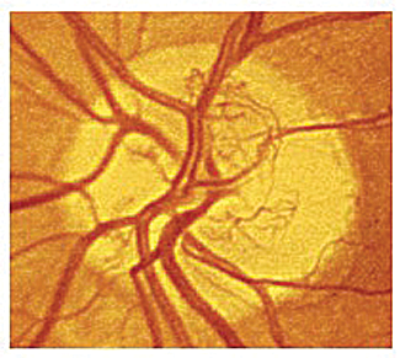

Figure 1: Standard photograph 10A showing new vessels at the disc covering

approximately 1/3 of the disc area. This constitutes high risk PDR requiring PRP [4].

- new vessels on or within one disc diameter of optic disc ≥1/3 disc area (Figure 1)